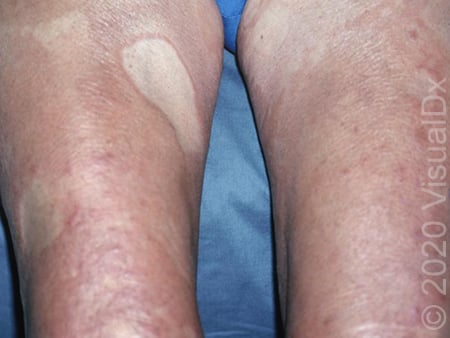

Morphea causes hardening of the skin more than color change, although it can appear lighter than the surrounding skin. This should be treated to avoid permanent changes in the skin of that area, as well as prevent new spots from forming.

Morphea_40393.jpg

Morphea